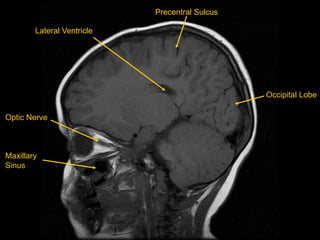

MRI BRAIN – T1 SAGITTAL

White Matter

Occipital Lobe

Cerebellum

Grey Matter

Frontal Lobe

Lateral Sulcus

Parietal Lobe

Temporal Lobe

Optic Nerve

Maxillary

Sinus

Precentral Sulcus

Lateral Ventricle